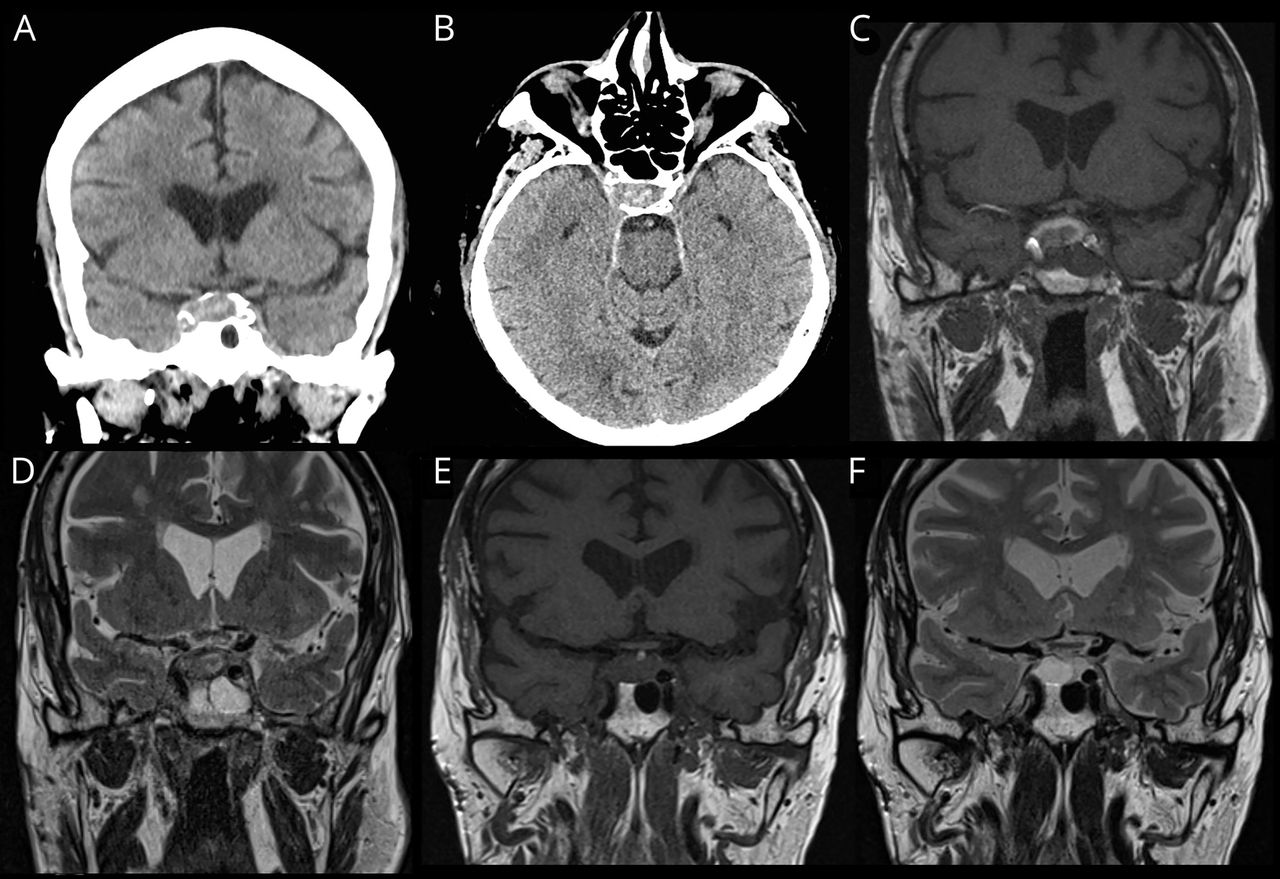

我们本地化的这些发现动眼神经的权利。鉴别诊断考虑这些结果包括沟通后动脉动脉瘤导致压第三神经麻痹了最初的严重性质的病人的头痛(10/10)、微血管第三神经麻痹了他的血管危险因素,垂体卒中(PA)的组合严重头痛和第三个神经麻痹,感染或转移给SCC和免疫抑制的历史,以及其他海绵窦病态像海绵窦血栓形成和Tolosa-Hunt综合症。实验室调查稀松平常的。病人的国际标准化比率是治疗。CT扫描的头部血管造影术(执行图2中,A和B)。在我们的独立审查的图像,我们怀疑可能错过sellar地区的病变。我们承认病人进行进一步的检查。

(一)冠状和(B)轴向CT显示sellar发现可疑病变。(C)冠状T1加权磁共振成像大脑sellar视图显示外围T1 hyperintensity笨重的脑下垂体,测量前后的1.7厘米由纵1.3厘米,2.1厘米中间外侧的横向延伸到上级的正确的海绵窦和对接上级和右颈内动脉的内侧方面。在日冕t2加权MRI (D)相应的视图。(E)冠状T1和T2 (F)冠状视图sellar内容的四个月随访MRI显示慢性血液制品除了垂体薄壁组织或肿瘤,现在测量1.3×2.0×1.1厘米。

病人接受MRI扫描与专用鞍视图,揭示T1 hyperintense信号涉及脑下垂体的发现符合亚急性出血鞍。这是符合PA腺瘤内(图2中,C和D),横向延伸到上级的正确的海绵窦和对接上级和右颈内动脉的内侧方面。而gadolinium-enhanced t1日冕序列通常是获得在这个环境中,我们的病人不能接受钆由于他严重的肾脏疾病。

神经外科团队商议,认为手术高危病人的并发症和推荐监测的临床进展。他也被称为内分泌学评价的二级垂体机能减退,其中包括血清我皮质醇,促甲状腺激素、免费T4、催乳素、胰岛素样生长因子1,促黄体激素,促卵泡激素,睾酮。没有缺肾上腺皮质,虽然患者已经服用强的松后肾移植。他要求左旋甲状腺素替代。他的复视和第三神经麻痹在2个月内解决。经过4个月的随访MRI显示轻微下降的大小sellar内容(图2中,D和E)。